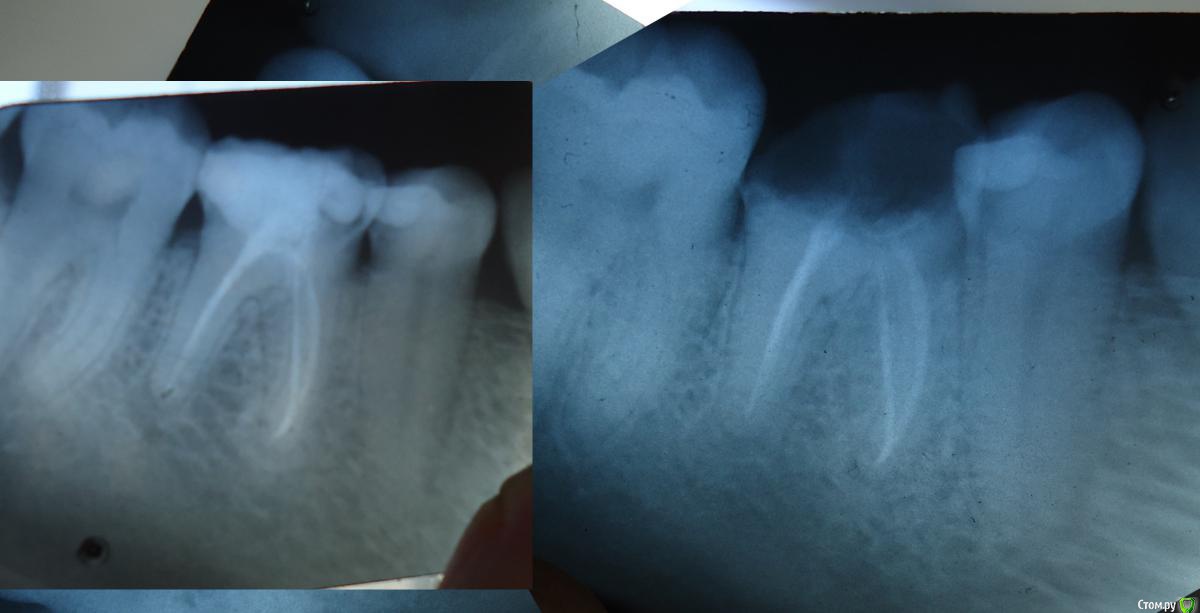

натg Опубликовано 21 апреля, 2015 Автор Поделиться Опубликовано 21 апреля, 2015 (изменено) Здравствуйте снова. Теперь возникла такая картинка- слева- зуб пол-года назад, справа - сейчас. Возник вопрос, что делать с корнем. Корень. под которым проблема, один. Предлагается его распломбировать методом Praf размягчитель , слелать в нем депофорез. Но говорят, это опасно, так как инструмент может сломаться, и еще есть вариант что корень не распломбируется. Еще говорят, что от распломбирования может быть обострение процесса и ухудшение. А если не распломбировать, простоит 10 лет максимум. Говорят, что если не удастся распломбировать, другого метода нет.Правда, говорят что через 10 лет может изобретут что-то. Для удешевления процесса предлагается распломбировывать и переделывать один канал, а не все три.. Что посоветуете? Какова, по Вашему мнению, вероятность, что распломбируется? Стоит ли туда лезть? Про шу не писать глубокомысленных замечаний, типа - глупостями занимаетесь и тд... Не тратьте свое время, на то, чтобы показать, что у меня нет диплома стоматолога, это и так очевидно.. Спасибо. фото возможно, некачественое, снимала фотиком.. Изменено 21 апреля, 2015 пользователем натg Ссылка на комментарий

St. Опубликовано 21 апреля, 2015 Поделиться Опубликовано 21 апреля, 2015 Если нет трещин по корню, то пытаться распломбировать ВСЕ каналы, и перепломбировать заново. Без депофореза. Вероятность успеха где-то 50/50. Потом коронка.Ничего не делая Вы гарантированно придете к удалению. Ссылка на комментарий

St. Опубликовано 21 апреля, 2015 Поделиться Опубликовано 21 апреля, 2015 То что таких симптомов нет - это хорошо. Трещины ищет врач зрительно когда начинает лечить Ваш зуб. Перелечивая все каналы получается более прогнрзируемый положительный результат. Поскольку пломба на зубе была негерметична, а сейчас как я понимаю её совсем нет в другие каналы могли попасть микробы. И соответственно потом спровоцировать обострение. Ссылка на комментарий

Zlata-doctor Опубликовано 11 мая, 2015 Поделиться Опубликовано 11 мая, 2015 1. Повторное эндолечение шестого зуба ( там есть очаг воспаления-это очевидно). Ищите хорошего эндодонтиста, если хотите иметь этот зуб. 2. Протезирование шестого зуба3. На первом снимке довольно большая полость 5 зуба ( живого), пораженная поверхность контактирует с 6 зубом, на втором снимке этой полости не видно, возможно потому, что снимок сделан с другого ракурса--еще раз сделать качественный снимок и подтвердить или опровергнуть мое предположение.4. Что вас заставляет спорить, как вы пишите, с врачом и упорно ходить "долепливать" одну и ту-же проблему? Ссылка на комментарий